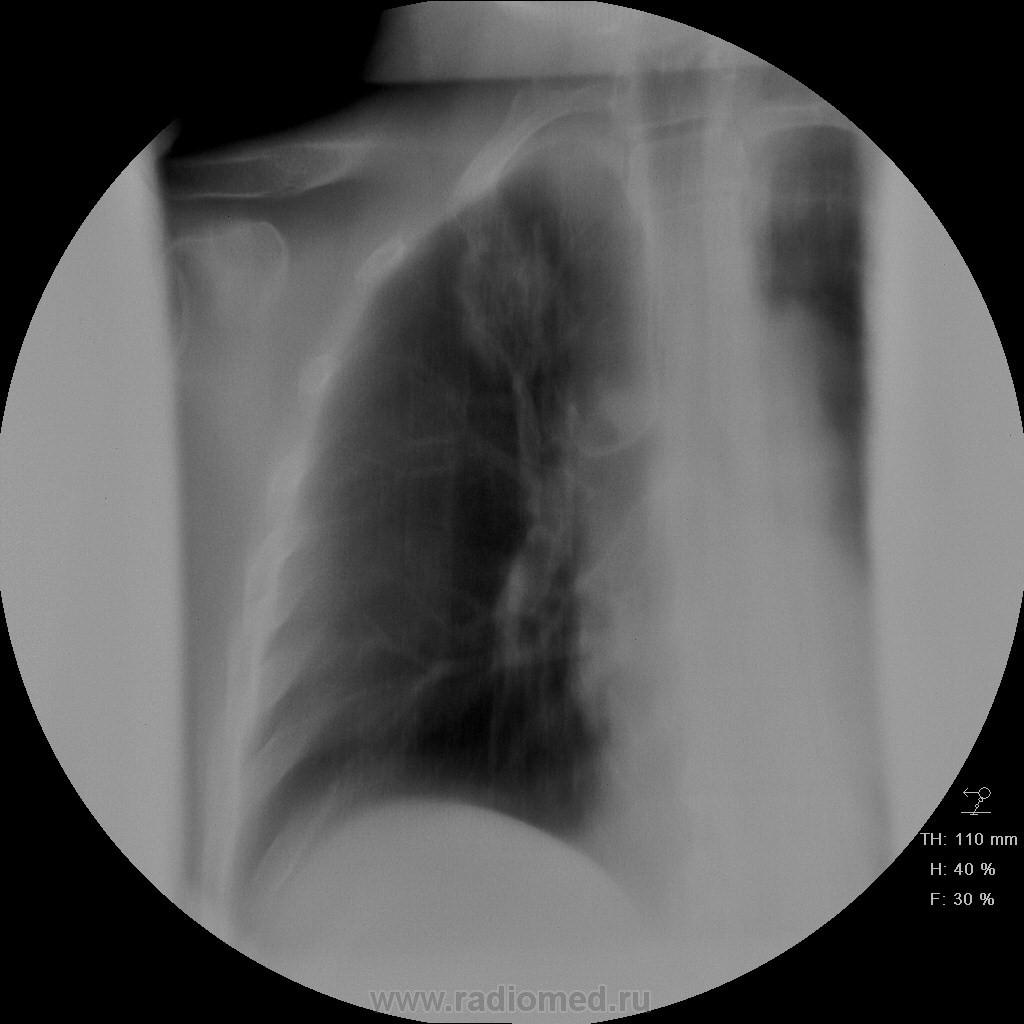

Пациет 60 лет после перенесения ОНМК. жалоб нет ( по легким) . СОЭ, лейкоциты, HB в норме.

Какие будут мнения.

КТ еще не запущен - так что выжимаем все из линейки...

У больных с последствиями ОНМК следует думать об аспирационном генезе заболевания. В пользу этого свидетельствует поражение задних сегментов и двусторонняя локализация изменений.